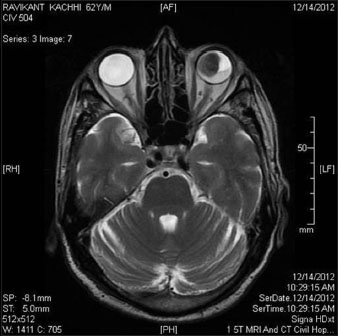

A 62-year-old male diagnosed with carcinoma of the left buccal mucosa in September 2012. He was operated upon (wide local excision of left buccal mucosa with left hemimandibulectomy and modified neck dissection type II) in September 2012. Histopathology report suggested squamous cell carcinoma of size 2.5 cm × 2.0 cm × 1.7 cm. All 31 lymph nodes dissected from left level I to V were free (0/31) of metastasis. No perineural or lymphovascular invasion was seen. Overlying skin was free. Depth of invasion was 0.7 cm. All the margins and cut end of bone were free. It was pathological stage pT2N0Mx. The metastatic workup at the time of surgery was negative for any distant metastasis. The patient was advised adjuvant radiotherapy (60 Gray in 30 fractions) from October 20, 2012 on a 6 MV linear accelerator with a two field wedge plan (Antero Posterior and Lateral field). During treatment (after 28 Gray/14 fractions), the patient presented with painless, gradually progressive diminution of vision of the left eye. A thorough ophthalmological examination was done which included slit lamp examination, ultrasonography (USG) of eyes, and magnetic resonance imaging (MRI) of both eyes and brain. Biopsy was not possible from the choroidal mass. The USG scan [Figure 1] revealed choroidal lesion suggestive of secondaries in the left eye. MRI brain and both eyes [Figure 2] and [Figure 3] showed the presence of altered signal intensity in the posterior chamber of the left eye which was hyperintense in T1-weighted sequence and hypointense on T2-weighted sequence. A solitary deposit in the left choroid involving 80% of the globe with secondary retinal detachment was seen. There was no other choroidal or brain metastasis. Positron emission tomography-computed tomography (PET-CT) evaluation showed metastatic disease in the left choroid, with no other involved site elsewhere in the body.

| Figure. 2 Magnetic resonance imaging scan of the left eye

| Figure. 2 Magnetic resonance imaging scan of both eyes and brain